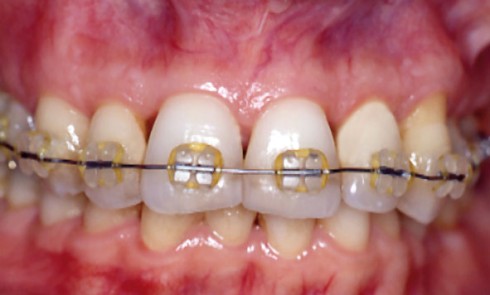

Article réservé à nos abonnés L’infiltration en profondeur – Partie II

D’autres équipes ont confirmé récemment nos premiers résultats [5, 3]. Toutefois, certaines taches n’étaient pas masquées par cette infiltration superficielle,...

Article réservé à nos abonnés Dossier Orthodontie prothèse

Au cours des trente dernières années, les avancées dans le domaine de la recherche ont permis une meilleure connaissance des...